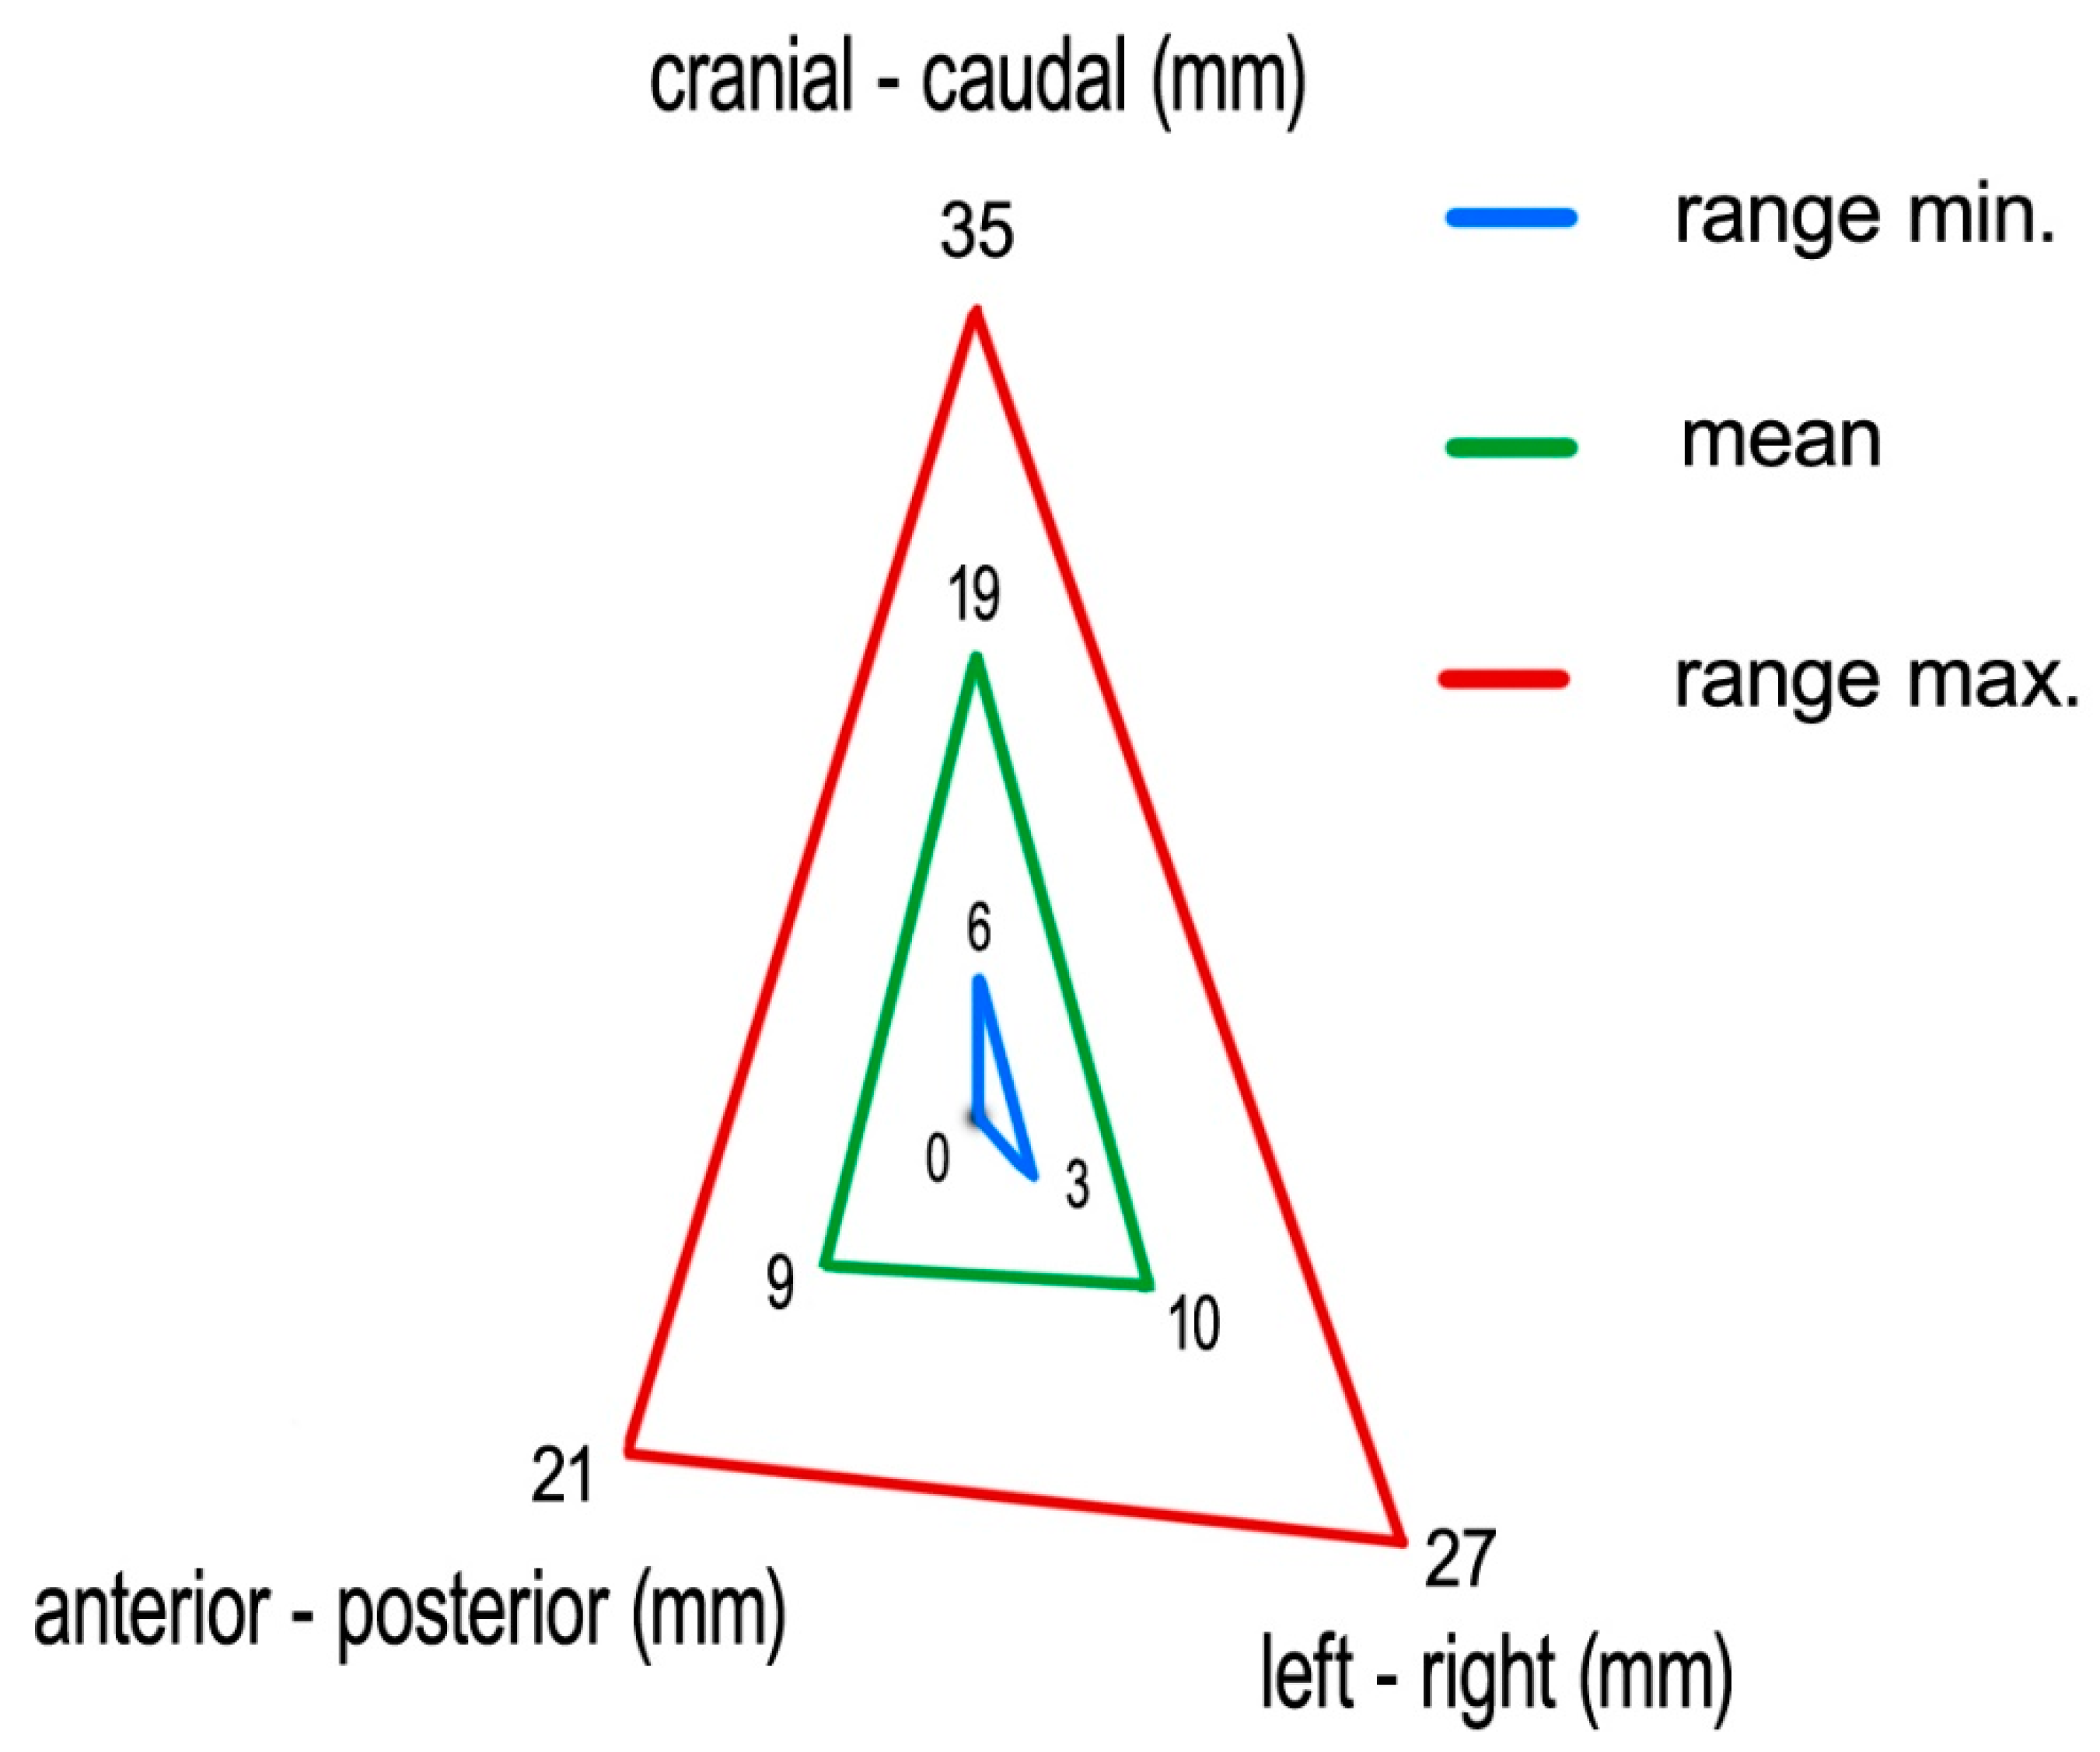

Measuring the 4D-CT study sets, we found following medians (means) of tumor excursions in the corresponding directions: CC: 19 (19) mm (ranging 6–35 mm), AP: 9 (9) mm (ranging 0–21 mm), and LR: 9 (10) mm (ranging 3–27 mm) (

Figure 6).